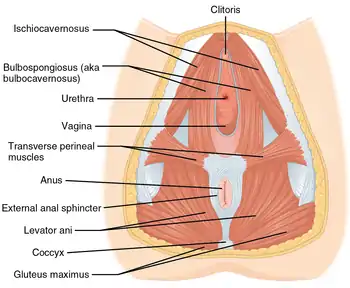

Pelvic floor

The pelvic floor has two inherently conflicting functions: One is to close the pelvic and abdominal cavities and bear the load of the visceral organs; the other is to control the openings of the rectum and urogenital organs that pierce the pelvic floor and make it weaker. To achieve both these tasks, the pelvic floor is composed of several overlapping sheets of muscles and connective tissues.[5]

The pelvic diaphragm is composed of the levator ani and the coccygeus muscle. These arise between the symphysis and the ischial spine and converge on the coccyx and the anococcygeal ligament which spans between the tip of the coccyx and the anal hiatus. This leaves a slit for the anal and urogenital openings. Because of the width of the genital aperture, which is wider in females, a second closing mechanism is required. The urogenital diaphragm consists mainly of the deep transverse perineal which arises from the inferior ischial and pubic rami and extends to the urogenital hiatus. The urogenital diaphragm is reinforced posteriorly by the superficial transverse perineal.[6]

The external anal and urethral sphincters close the anus and the urethra. The former is surrounded by the bulbospongiosus which narrows the vaginal introitus in females and surrounds the corpus spongiosum in males. Ischiocavernosus squeezes blood into the corpus cavernosum penis and clitoridis.[7]